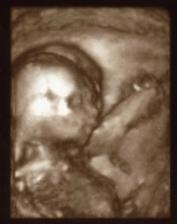

18.2.2009 další kontrola, mimís měří 11,9 mm, srdíčko šlape jak hodinky, máme zase fotku a opět kresbu od pana doktora jako bonus 🙂)